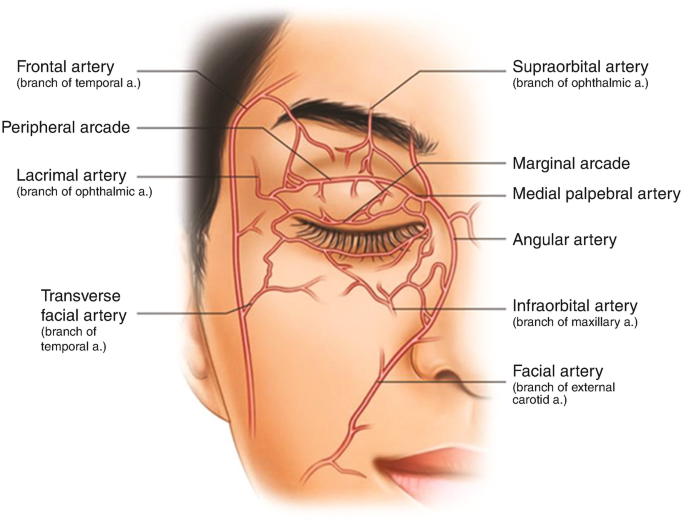

1. Infra & Supraorbital area

The eye area is one of the most vascular areas on your face, there’s several nerves & arteries running through the area. Injections are done in MICRODROPLETS in this area, they’re injected bone-deep or just above the bone, since that region already has a good blood supply for the fat to connect to and because this decreases the chances of lumps of fat being visible texture.

A small real-time ultrasound is common practice to find where arteries are for filler injections. This is not a guarantee at all though, this would just be good to see what areas are most populated with vessels, the likelihood of you using an ultrasound to accurately map out where all the vessels on your face are are close to zero.

The main risk when injecting anything solid into somebody, like filler or fat, is a vascular occlusion, a vascular occlusion is when a foreign substance either fills an artery/vessel, or sits next to it and puts enough pressure onto it to clog it and slow down or block blood flow. With filler this is reversible using hyaluronidase, in this instance with fat it is not possible to reverse or dissolve fat if you get it stuck inside.

Using a cannula, you’re able to evenly spread out the microdroplets of fat through different areas, the logic behind injecting microdroplets should be obvious, the less you’re injecting at once the less likely you are to inject a large enough amount to block off vessels.

On both the supra & infraorbital region you want to place the fat graft on the bone itself or a tiny bit above the bone. I would not recommend even attempting to DIY this if you haven’t already had filler done professionally, or preferably DIY’d filler by this point.

1. Infra & Supraorbital area

The eye area is one of the most vascular areas on your face, there’s several nerves & arteries running through the area. Injections are done in MICRODROPLETS in this area, they’re injected bone-deep or just above the bone, since that region already has a good blood supply for the fat to connect to and because this decreases the chances of lumps of fat being visible texture.

A small real-time ultrasound is common practice to find where arteries are for filler injections. This is not a guarantee at all though, this would just be good to see what areas are most populated with vessels, the likelihood of you using an ultrasound to accurately map out where all the vessels on your face are are close to zero.

The main risk when injecting anything solid into somebody, like filler or fat, is a vascular occlusion, a vascular occlusion is when a foreign substance either fills an artery/vessel, or sits next to it and puts enough pressure onto it to clog it and slow down or block blood flow. With filler this is reversible using hyaluronidase, in this instance with fat it is not possible to reverse or dissolve fat if you get it stuck inside.

Using a cannula, you’re able to evenly spread out the microdroplets of fat through different areas, the logic behind injecting microdroplets should be obvious, the less you’re injecting at once the less likely you are to inject a large enough amount to block off vessels.

On both the supra & infraorbital region you want to place the fat graft on the bone itself or a tiny bit above the bone. I would not recommend even attempting to DIY this if you haven’t already had filler done professionally, or preferably DIY’d filler by this point.